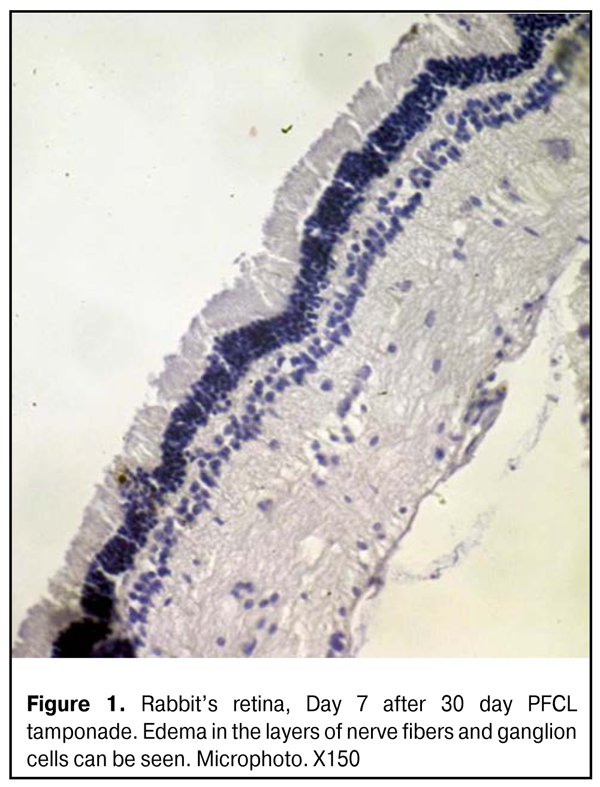

Parameters of photoreceptor layer in the central retina didn’t differ significantly, according to the data of Photoptic ERG. Furthermore, inner retina activity was not significantly changed (b-wave parameters). Thus, b-wave amplitude was not increased significantly as compared to initial one and was equal to 80.5±7.5 (µV); however, implicit time increased to 40.2±2.2 (ms) (р=0.001). Flicker ERG revealed an increase of photoptic response N1-P1 wave amplitude to 47.0±3.0 (µV) (р=0.07) and increased implicit time (63.2±2.1 ms (р=0.01)) (Tables 1, 2). Hence, a week after PFCL removal, a reaction of response activation to light stimulus was revealed in the middle retinal layers; that was manifested in increased ERG amplitude (supernormal ERG) though accompanied by decreased potentials. Thus, there was detected excessive irritability of the retina, i.e. changes in the physiological parameters, increasing their offset without prior external exposure. LOM didn’t reveal any significant changes in the retinal structure, despite edema in the nerve fiber and ganglion cell layers, at all time points (Fig.1).

At Days 7-14, the ultrastructure of the retinal pigment epithelium (RPE) didn’t differ from the normal one, despite single cells, in which cytoplasm structure vacuolization was observed. No alterations were seen in photoreceptor cells (PC) at this time point. Neurons and nerve structures of the inner retinal layers didn’t differ as well. In cytoplasm of M?ller cell process (MCP) in the inner limiting membrane (ILM), osmiophilic granules were noted, that made the structure of MCP different from the normal one (Fig.2).